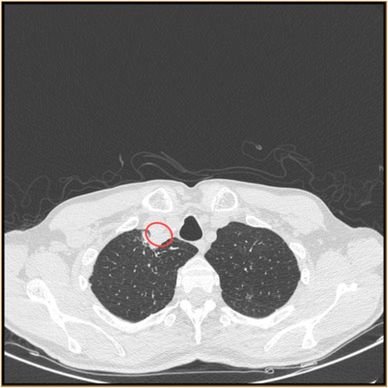

U pacjenta wykryto za pomocą badania TK ropień okołotchawiczy

U pacjenta wykryto za pomocą badania TK ropień okołotchawiczy © Medical Mycology Case Reports

Tomografia komputerowa ujawniła ropień okołotchawiczy. Lekarze dokonali aspiracji materiału, a badania początkowo nie ujawniły, jakiego rodzaju infekcja grzybicza doprowadziła do powstania ropnia. Ostatecznie próbkę odesłano Centrum Informacji i Badań nad Grzybami o znaczeniu medycznym należącego do Światowej Organizacji Zdrowia (WHO), gdzie sekwencjonowanie DNA ujawniło właśnie chrząstkoskórnika purpurowego.